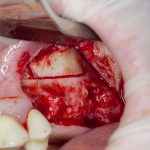

Для получения костного блока, мы открываем донорскую зону, наружную косую линию нижней челюсти.

Получение костного аутотрансплантата.

Здесь потребуется пародонтологический зонд с миллиметровой разметкой или какой-то другой измерительный прибор (операционная линейка). Ранее по КЛКТ я измерил костный дефект, теперь нужно нанести границы будущего костного блока на донорскую зону.

Для получения костного блока мы использовали ультразвуковую пьезохирургическую систему. Это самый удобный и безопасный инструмент для проведения подобных манипуляций. С помощью него мы сформировали и выделили костный блок. Он должен отделяться легким движением остеотома или элеватора. Как это сделать правильно — читай здесь>>